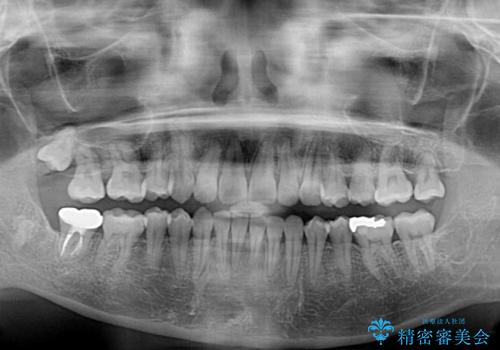

上顎の正中位置をほぼ保った状態で、綺麗に仕上げることができました。